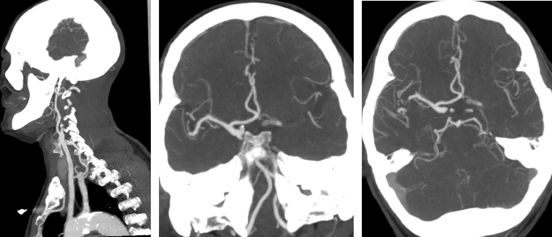

CTA示左侧颈内动脉起始部闭塞,ICA末端显影,大脑中动脉M1闭塞。